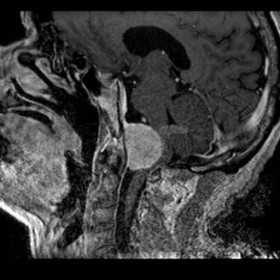

Si avvale di vie di accesso fino a pochi anni fa sconosciute, che si fanno strada attraverso le strutture ossee, nervose e vascolari della base del cranio, e che permettono di raggiungere la patologia senza porre alcuna trazione o compressione sulle strutture vitali del cervello.

A causa della complessità della via di accesso, al fine di non ledere le fragili e delicate strutture della base cranica, ogni intervento viene affrontato con l'ausilio del monitoraggio neurofisiologico intraoperatorio e talora della neuronavigazione.